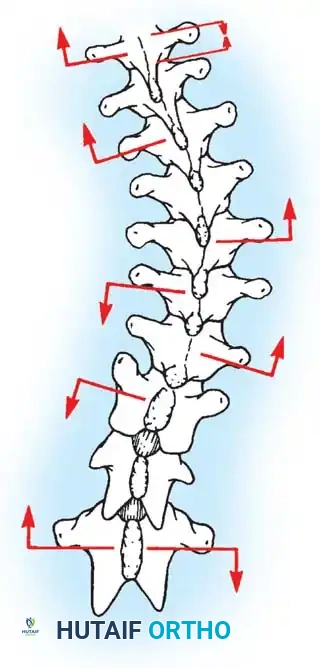

Fig. 38-24: Posterior view of segmental vessels located just lateral to each facet joint, requiring meticulous coagulation.

Lateral Exposure and Hemostasis

- Transverse Process Exposure: Extend the subperiosteal dissection laterally, first exposing the facet joints, and then continuing out to the tips of the transverse processes bilaterally.

- Segmental Vessels: As you dissect lateral to the facet joints, you will encounter the posterior branches of the segmental vessels. These must be meticulously identified and coagulated with bipolar or monopolar cautery to prevent insidious bleeding.

- Facet Cleaning: Use a sharp curet and a pituitary rongeur to completely excise the facet capsules and clean the interspinous ligaments.